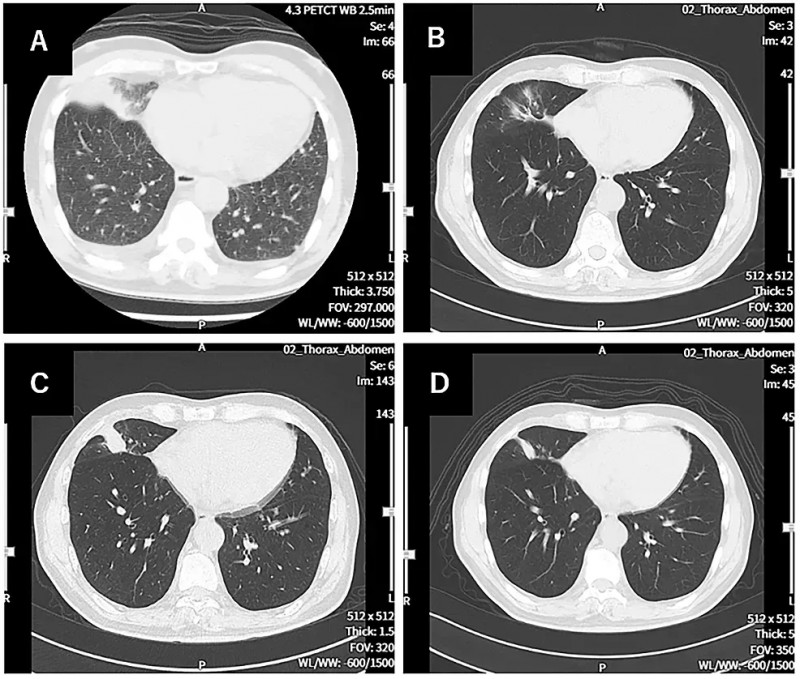

此外,肺部病灶也有显著变化,对比治疗开始时(第0天)的胸部CT,治疗第114天的胸部CT显示患者肺部肿瘤明显缩小(详见下图)。在肿瘤标志物方面,患者确诊时癌胚抗原(CEA)高达66.4,而治疗第121天骤降至3.0。截至数据统计时,该患者的无进展生存期(PFS)已超577天,且临床状况良好,体能状态评分为1。

▲图源“Cureus”,版权归原作者所有,如无意中侵犯了知识产权,请联系我们删除